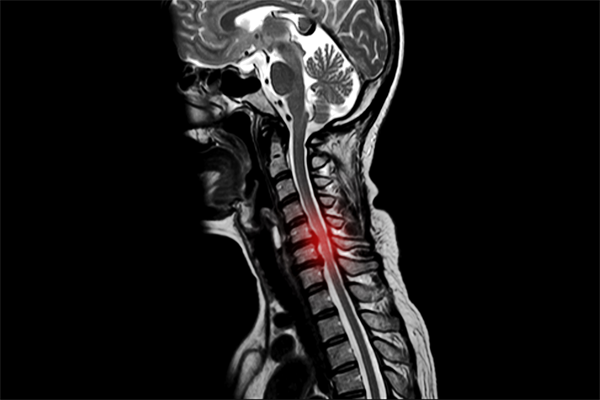

척추에는 뼈의 정렬과 움직임 그리고 안정감을 담당하기 위함으로 지지대 역할을 하는 여러 인대가 존재해요. 전형적으로 척추 전방의 전종인대와 후방의 후종인대를 들 수 있어요. 척추는 목 부위의 경추부터 꼬리뼈 주위 천추에 이르는 33개의 뼈로 되어 있으며 척추관은 척추 가운데 관 형상의 빈 공간으로 척추관 속에는 뇌로부터 팔다리까지 신경이 지나가는 통로라고 할수 있습니다.

목디스크가 생기면 경추 사이 디스크가 밀려나오며 팔이나 손가락으로 걸치는 신경을 눌러서 억누르게 됩니다 하더라고요. 압박증상으로 말미암아 해당 부위의 감각이 둔해지며 척추가 불안정하게도면 부근에 자리한 관절까지 영향을 미치게 돼 바랍니다. 그러면서 어깨 통증도 나타나게 되지만 이러한 어깨 통증을 느끼시면 오십견 등의 어깨질환과 혼동할 수 있다고 하지만 머리 뒤에 손을 얹는 동작을 하면 통증이 감퇴하는 경우도 있어서 목디스크로 의심을 해보시고 진료를 받아보시는 걸 권장드립니다.

목의 디스크가 손상이 일어나서 부근 신경을 자극하여 심각한 통증을 같이할수 있는데요 통증은 상식적으로 목의 한쪽 면에 유발되며, 어깨나 팔까지 타나날 수 있습니다.